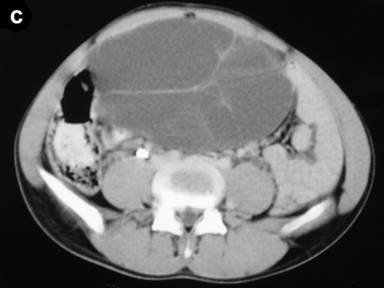

Clinical examination revealed abdominal swelling with generalized tenderness occupying the whole abdomen and almost reaching up to the pelvis. Blood investigation revealed polymorphonuclear leukocytosis (total leukocyte count 12,600 mm-3, reference range: 4,000-11,000 mm-3; polymorphs 91%, reference range: 40-75%). The serum amylase level was 297 U/L (reference range: 20-85 U/L). Liver function tests and CA 19-9 levels were normal. An ultrasound carried out outside our hospital found a large septate cystic collection in front of the pancreas and reported as acute pancreatitis with fluid collection. A CT scan revealed a large multiseptate cystic lesion (23.2x11.7x26.2 cm) anterior to the pancreas reaching up to the pelvis and displacing the gut loops behind and downwards (Figures 1 and 2). We decided to perform a laparotomy with a presumptive diagnosis of cystic neoplasm of the pancreas.

Figure 1. CECT axial scans showing a multiseptate cystic tumor anterior to the pancreas and reaching up to the pelvis. |